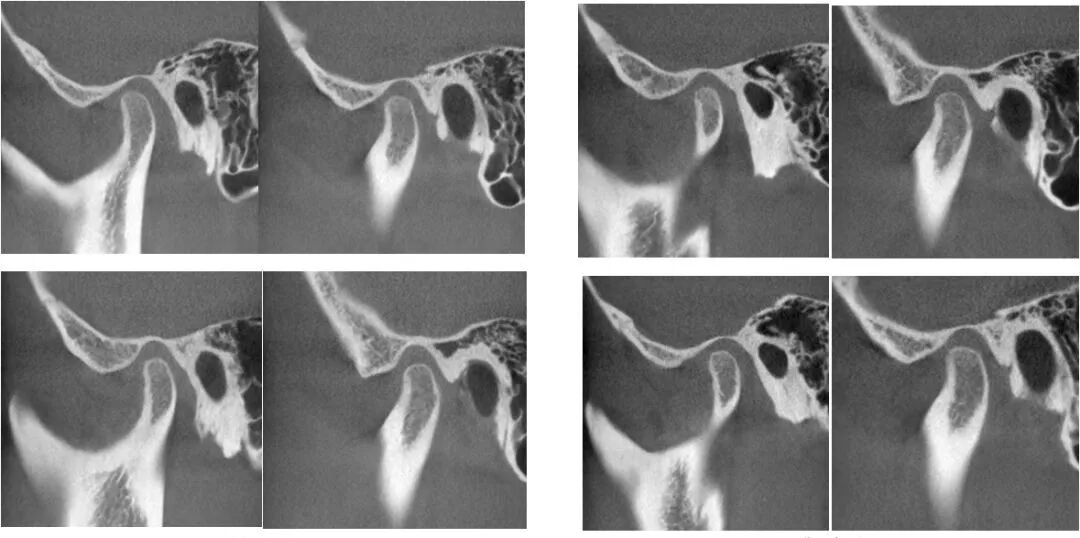

CBCT检查:

从患者双侧颞下颌关节的ct断层影像上看,右侧关节前间隙明显偏小,髁突表面骨皮质较连续但厚度较薄,右侧关节间隙较均匀,个别断面上,髁突表面的骨皮质较粗糙,不明显。左侧颞下颌关节髁突表面骨皮质模糊粗糙,厚度较薄,关节间隙较均匀。临床功能检查上,患者开口度开口型正常,双侧关节张口中期有弹响。

右侧颞下颌关节髁突表面骨皮质连续均匀,关节间隙均匀。左侧颞下颌关节髁突表面骨皮质增厚,个别吸收点消失,关节间隙较均匀。